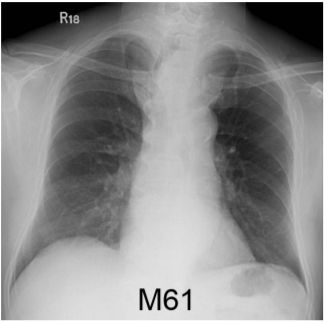

4. 男性,61歲,有吸煙史,主訴咳嗽和喘,胸部X光如圖,下列何種診斷最可能? (A) 鱗狀細胞肺癌 (B) 小細胞肺癌 (C) 淋巴瘤 (D) 主動脈瘤 (E) 甲狀腺腫